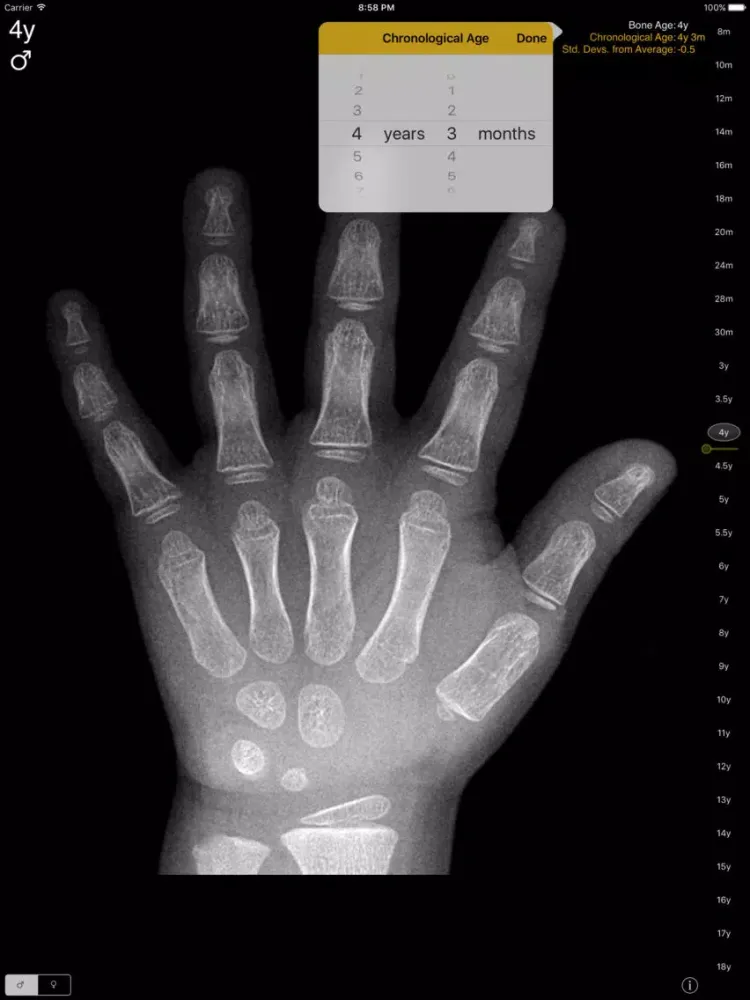

The Gilsanz and Ratib digital Hand Bone Age atlas for iPad, iPhone and iPod Touch brings this essential radiology reference to radiologists, endocrinologists, and pediatricians on the move.

In the past, determination of bone maturity relied on visual evaluation of skeletal development in the hand and wrist, most commonly using the Greulich and Pyle atlas. The Gilsanz and Ratib digital atlas takes advantage of digital imaging and provides a more effective and objective approach to assessment of skeletal maturity.

The atlas integrates the key morphological features of ossification in the bones of the hand and wrist and provides idealized, sex- and age-specific images of skeletal development.

Hand Bone Age: A Digital Atlas of Skeletal Maturity,2e, Vicente Gilsanz, Osman Ratib, ISBN 978-3-642-23761-4